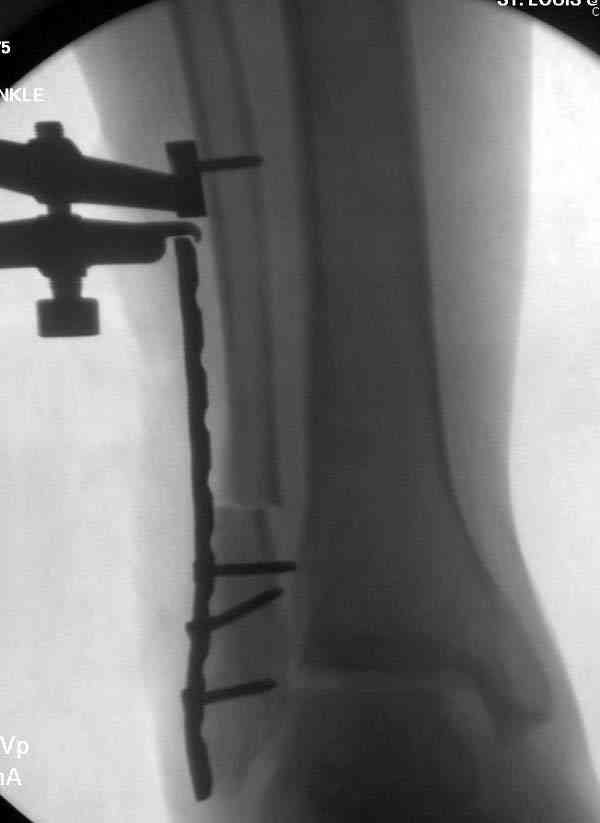

Здесь представлено решение похожей проблемы. Больной в течение года

лечился консервативными мерами, и боли в голеностопе были основным

показанием к операции.

Проведена обычная стандартная процедура по исправлению

неудовлетворительного состояния голеностопного сустава, где кроме

удлинения малоберцовой с применением compression tension device за

проксимальный конец пластины, проведено замещение трикортикальным

графтом из крыла, освобождение синдесмоза и медиальной щели от

фибротических масс с фиксацией.